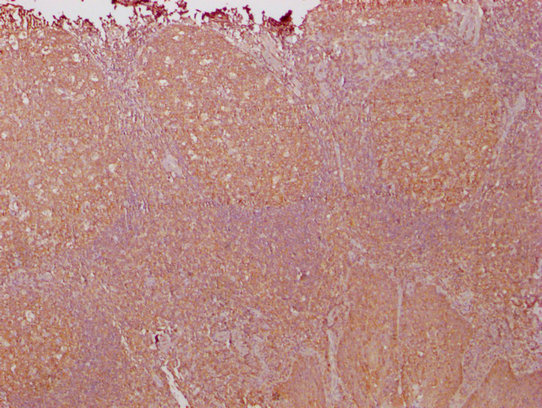

IHC image of CSB-MA018072A1m diluted at 1:1000 and staining in paraffin-embedded human tonsil tissue performed on a Leica BondTM system. After dewaxing and hydration, antigen retrieval was mediated by high pressure in a citrate buffer (pH 6.0). Section was blocked with 10% normal goat serum 30min at RT. Then primary antibody (1% BSA) was incubated at 4°C overnight. The primary is detected by a biotinylated secondary antibody and visualized using an HRP conjugated SP system.

-